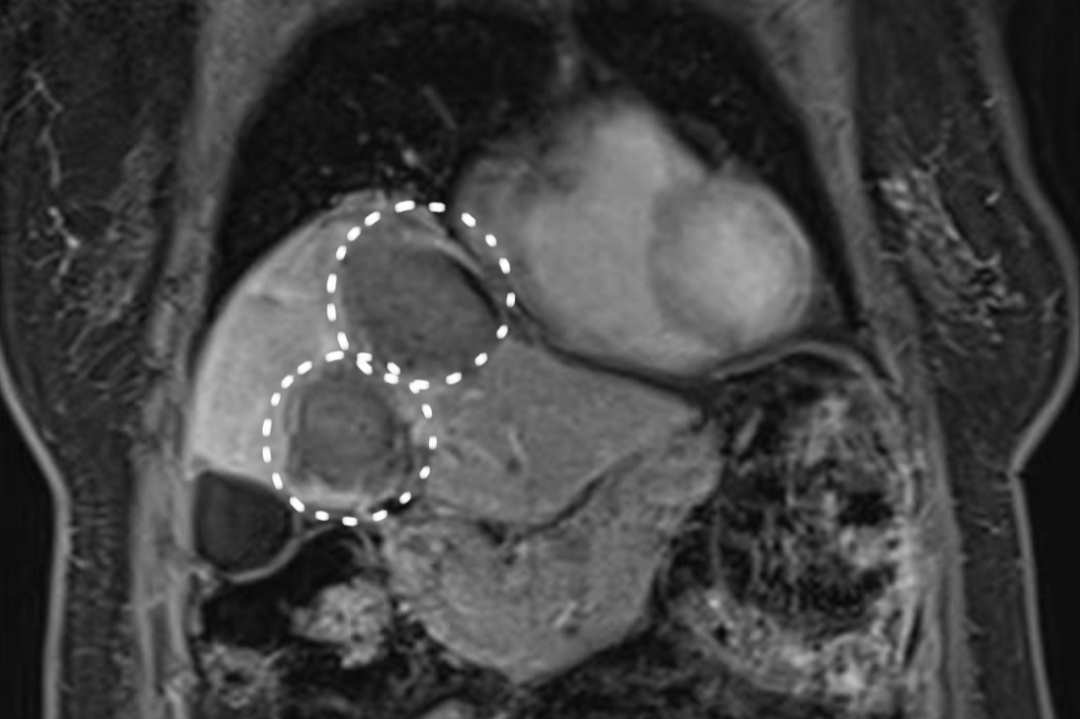

患者术后第二天MR

复查结果提示未见肝内有强化病灶,肿瘤完全失去了活性。经外周静脉注射造影剂Sonazoid后,病灶区域始终未灌注区,显示消融效果满意。